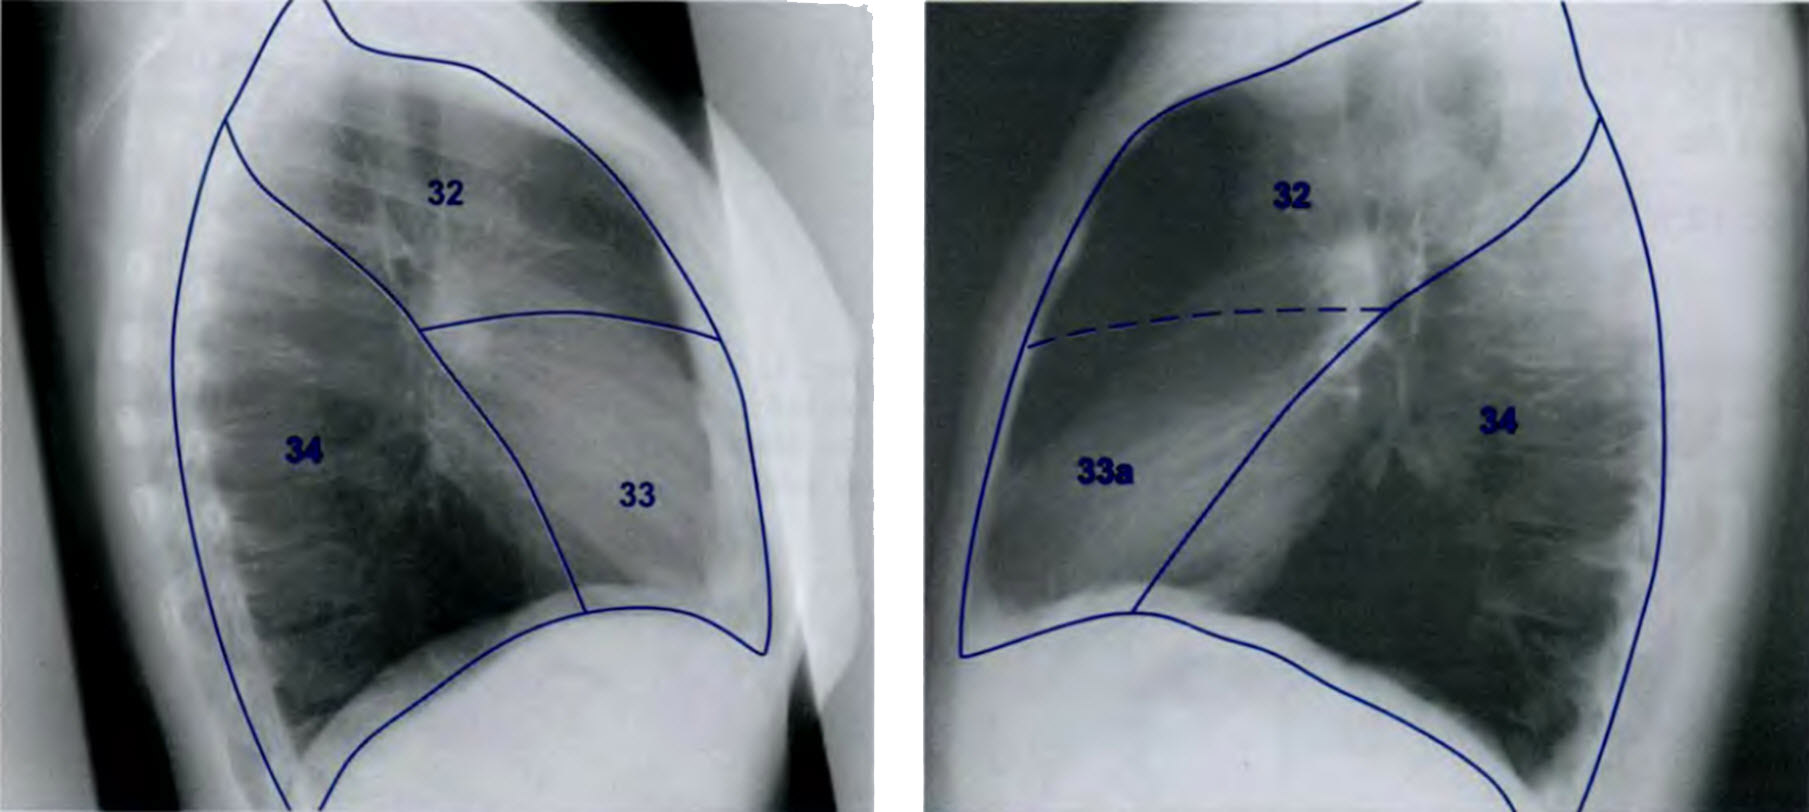

Анатомические изображения сегментов легких различных животных

Раздел: Другие животные